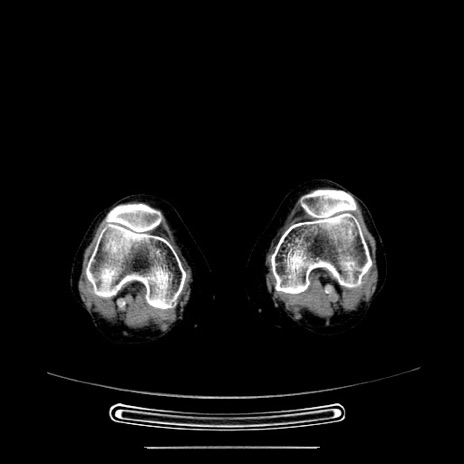

冠状断像

【症例】70歳代女性

【主訴】お腹が張る

【現病歴】1週間くらい前から腹部膨満の自覚あり。昨日夜から増悪したため、本日救急外来受診。

【身体所見】意識清明、BT 36.5℃、BP 165/106mmHg、HR 80bpm、SpO2 98%、腹部:膨満、軟、自発痛・圧痛なし、触診にて不快感あり、腸蠕動音:減弱

【データ】WBC 12600、CRP 1.04